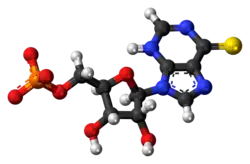

3D model (JSmol)

Thioinosinic acid (or thioinosine monophosphate, TIMP) is an intermediate metabolite of azathioprine, an immunosuppressive drug.[1][2]